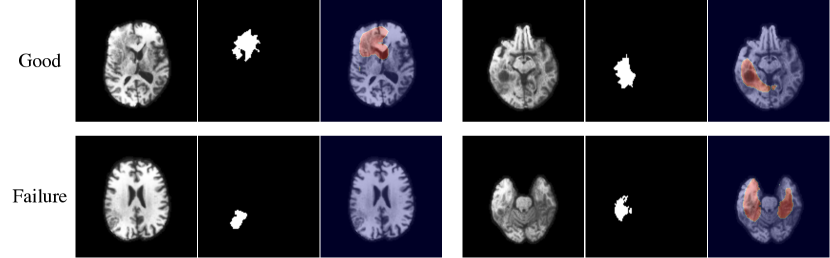

While working in multi-channel feature spaces improves robustness and performance of anomaly detection methods for brain MRI, the loss of spatial resolution through the feature mapping function leads to coarse segmentations and can cause models to miss small anomalies as shown in Figure 5. Another failure case shown here happens at slices far away from the center of the brain. Since the structure there differs significantly from the rest of the brain, large regions get misclassified as anomalous.

Refer to caption

Figure 5: Two successful samples (first row) and two failure cases (second row). On the left, the model fails to detect a small anomaly. On the right, a slice far away from the center shows false positives. Each with input image, manual segmentation, and anomaly map thresholded at t=0.75𝑡0.75t=0.75 from left to right.